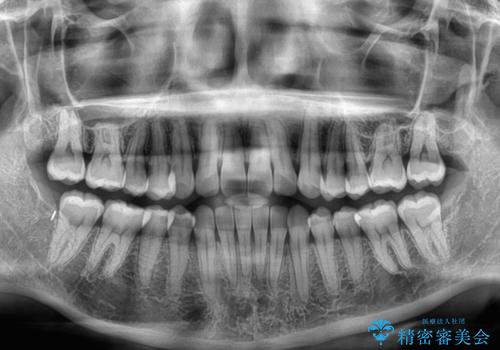

- 上下前歯の叢生を気にして来院された患者様です。

インビザラインでの治療を希望されていて、デコボコの程度が中等度であり、安価なパッケージにて対応可能と判断されたため、インビザライン・モデレートを用いて矯正治療を行うこととしました。